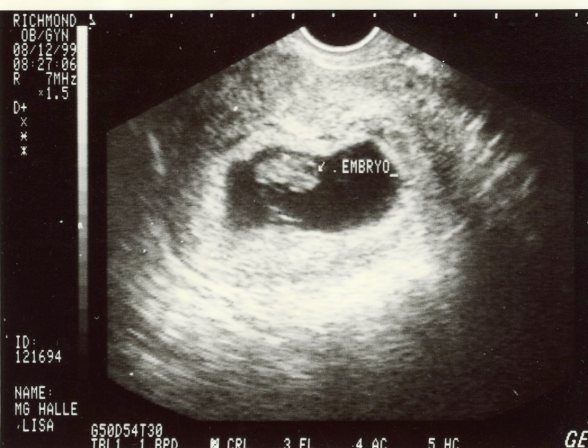

Dane’s Ultrasound | 08/12/99